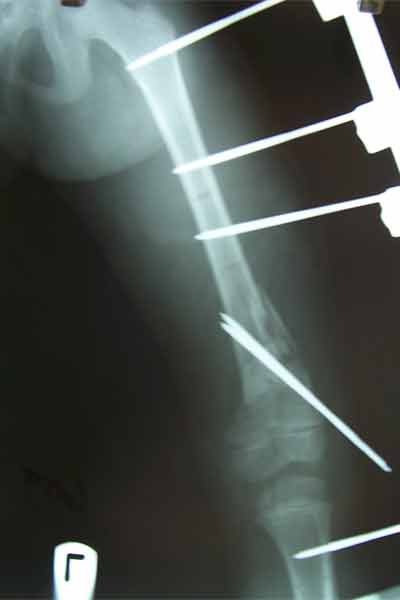

Case:8 Polytrauma

Patient having closed segmented fracture midshaft & lower 1/3 Tibia with closed fracture superior & inferior pubic rami right side with pelvis fracture following vehicular accident wastreated with intramedullary nail for fracture tibia and external fixator for fracture pelvis.

Pre-Op

Immdiate Post-op

Post-op Lateral